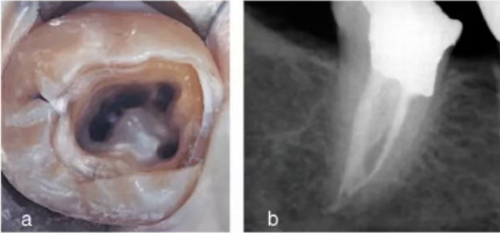

使用手術(shù)顯微鏡是非常有幫助的,特別是在那些根管口被鈣化物覆蓋的病例中,這些鈣化物可以使用超聲尖或長柄小球鉆輕松去除(圖 14a-d)。

大部分 C 型根管系統(tǒng)在根管口處為連續(xù)的 C 型結(jié)構(gòu);但是,沿著牙齒牙根方向,橫截面形狀可能是 C1,C2 或 C3 的任一種。C4 和 C5 幾乎只能在根尖附近的橫截面見到(圖 15a-c)。C 型根管的下頜磨牙在清理、預(yù)備成型及充填方面都存在挑戰(zhàn),特別是,當(dāng)髓室底發(fā)現(xiàn)C 型根管口時,不能確定根管在到達牙根根尖 1/3 時是否是連續(xù)的。在定位 C 型根管系統(tǒng)主根管分叉為兩根管或三根管的部位及識別根管間的峽部時,手術(shù)顯微鏡是很有幫助的(圖16a-b)。C 型根管沖洗時應(yīng)盡量使用超聲銼活化沖洗液。

事實上,在根管充填前進行 1 分鐘的超聲蕩洗可以增加根管及峽部的清潔程度。應(yīng)使用熱牙膠垂直加壓技術(shù)充填C 型根管,特別是在這些困難的錯綜復(fù)雜的根管系統(tǒng)中,也能完成三維的根管充填(圖 17a、b)。